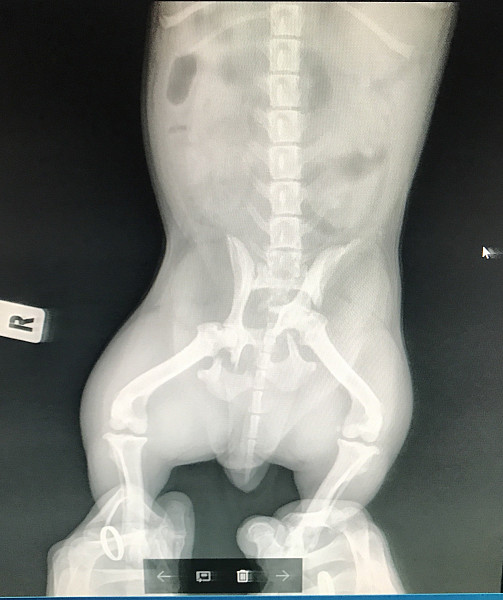

Перелом таза у собаки

Перелом таза у собаки 139 фотографий